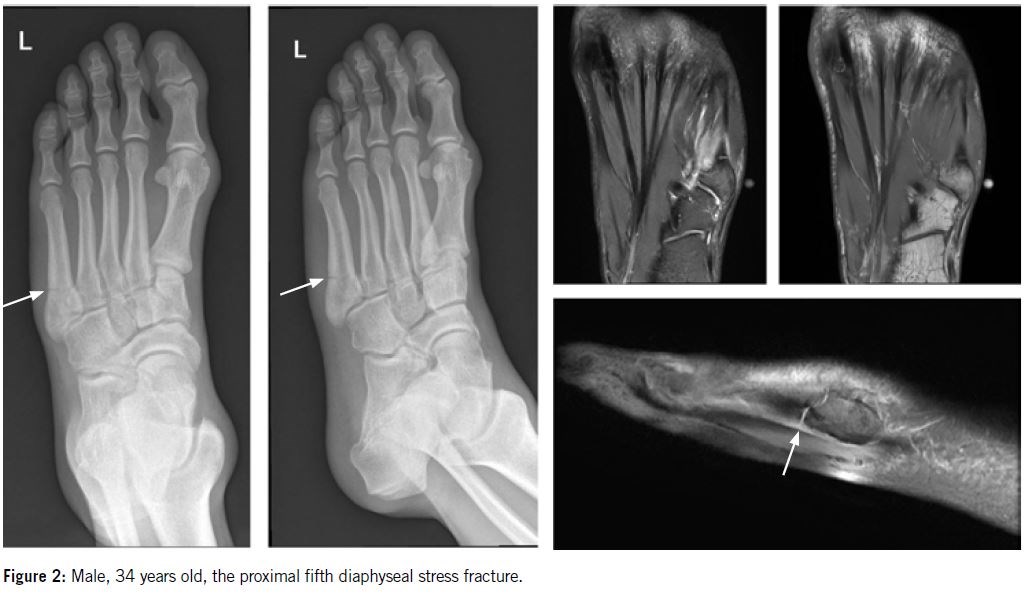

Proximal fifth metatarsal diaphyseal stress fracture present prodromal symptoms and typical radiograph features that differs from the clear radiolucent line in an acute fracture (Figure 2).

Weight bearing anterior-posterior, lateral and oblique views of the foot need to be included in the radiological request. The initial stage may not show any changes on radiograph, but later stages, periosteal reaction and callus formation are apparent.

MRI

MRI is especially helpful in the early stage in managing athletes at risk. It allows early recognition of bony edema before a fracture becomes evident and allows measures to be taken to prevent development of a frank stress fracture.